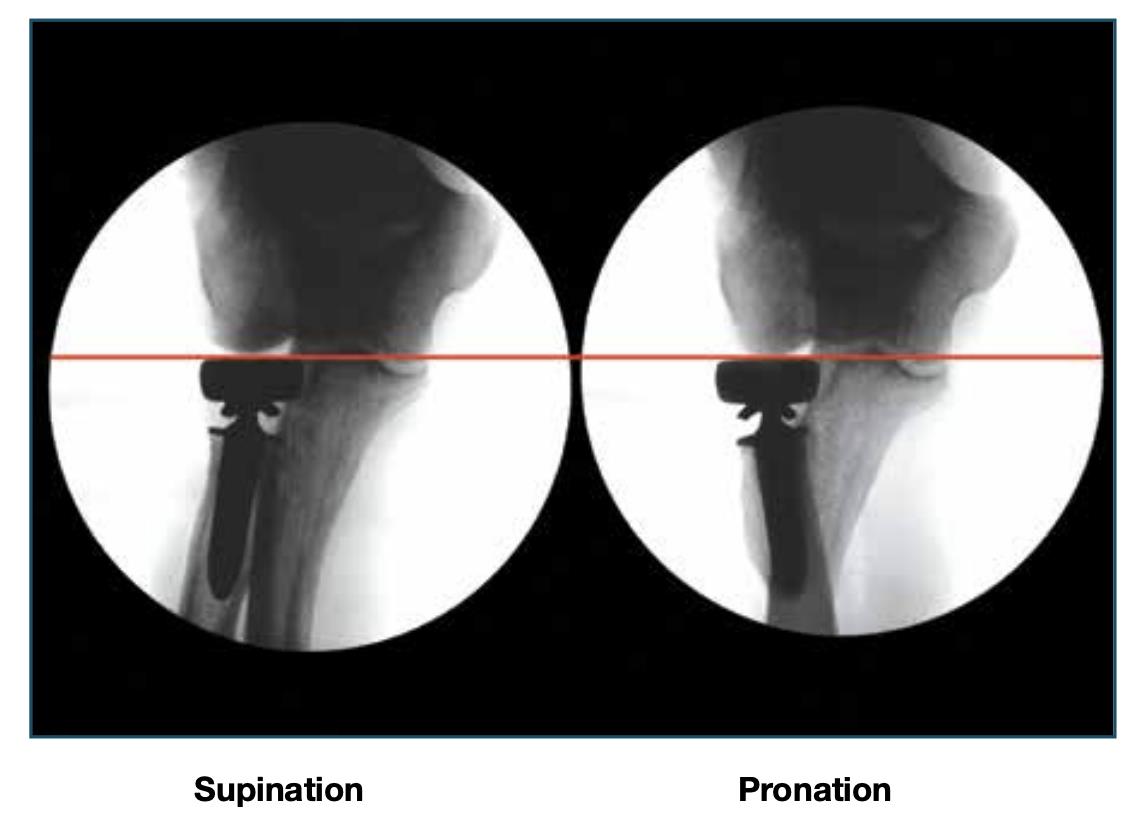

• Fluoroscopic Confirmation

• confirm a proper fit using fluoroscopy, then remove the trial components

• A

• in a true A/P view of the proximal forearm in supination, confirm that the height of the radial head trial is at or distal to the corner formed by the lesser and greater sigmoid notches

• B

• also, confirm proper radial head diameter by assuring that the apex of the capitellum is centered over the radial head

• confirm final implant alignment using fluoroscopic imaging